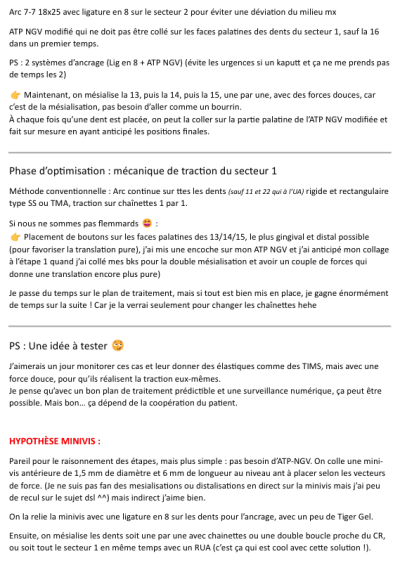

Solution bonus en minivis :

Je fais un ATP-V avec mini vis d’ancrage palatin que je fais un peu plus svt (gnrlmt utiliser après un pendulum de Hilgers modifié) et du coups je peux reproduire la meme solution que j’avais dis avec le ngv mais cette fois avec une solution mini vis et donc + d’ancrage

Solution Bonus – ATP-V modifié

Une base squelettique en 0.36, à vérifier pour s’assurer qu’elle est suffisamment rigide.

La face palatine des dents du secteur 1 est collée. Il s’agit de bases reliées à un anneau sur la barre palatine, avec des chaînettes permettant de tracter les dents une à une.

Un prolongement est ajouté à l’arrière des incisives maxillaires, ainsi qu’un autre partant de la face distale de la 11 jusqu’au niveau vestibulaire. Ce dispositif vise à limiter les mouvements parasites. Étant donné que les dents 13/14/15 et 16 ne seront pas directement prises en charge dans l’Ac, mais uniquement tractées par l’ATP-V, ces mouvements parasites resteront présents, bien que réduits à un taux tres faibles par rapport à tous les systèmes grâce notre traction direct sur l’ATP-V et sans prise en charge dans l’Ac des dents tractées.

Certes, cet appareil sur mesure représente un coût légèrement supérieur, mais il permet un gain de temps au fauteuil en ne nécessitant que le changement des chaînettes. De plus, il assure une efficacité accrue, permettant ainsi de se concentrer sur d’autres aspects du traitement.